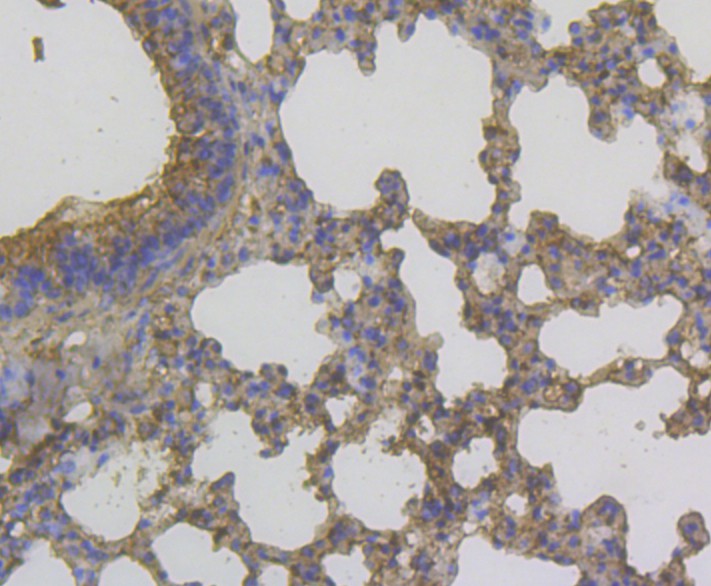

Application: IF-Tissue

Species: Mouse

Site: lung

Sample: Paraffin-embedded section

Antibody concentration: 1/200

Immunohistochemical analysis of paraffin-embedded mouse lung tissue using anti-YKL-40 / CHI3L1 antibody. The section was pre-treated using heat mediated antigen retrieval with Tris-EDTA buffer (pH 8.0-8.4) for 20 minutes.The tissues were blocked in 5% BSA for 30 minutes at room temperature, washed with ddH2O and PBS, and then probed with the antibody (EM1902-14) at 1/200 dilution, for 30 minutes at room temperature and detected using an HRP conjugated compact polymer system. DAB was used as the chrogen. Counter stained with hematoxylin and mounted with DPX.